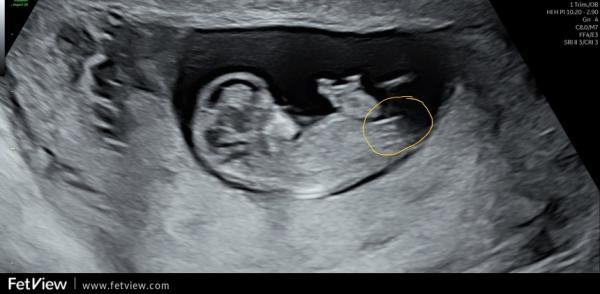

Oh, ich bin ja ganz bei dir. Finde das auch total spannend. Auch wenn das natürlich keine 100% Garantie gibt. Ich muss gestehen, dass ich mich danach ein wenig reingelesen habe und das Ganze trotzdem nicht 100% verstanden habe 🤔😃 Meine Bilder sind aber auch nicht so eindeutig, wie die, die man im Internet (meist) findet. Gerade beim letzten Bild hätte ich eher auf ein Mädchen getippt, weil das für mich so parallel aussah, wo ich eingekreist habe 🥰 Der weiße "Strich/Fleck" oberhalb von dem orangenen Kreis gehört zum Bein. 🤭 Einfach spannend 😍

Ich find es halt interessant, weil die Ärztin bei der Feindiagnostik auch damit anfing und das nochmal erklärt hatte. Schade, dass man den Nub nicht so genau erkennen kann. Oder man kann ihn sehen aber unser ungeschultes Auge bekommt es nicht gebacken 😂 Ich weiß was du meinst. Hab dein Bild frecher weise einfach mal "bemalt" um zu zeigen, was ich meine.

Genau. Das letzte Bild war es. Der untere Strich geht nach unten, der obere nach oben. Es sind nicht beide Parallel verlaufend nach unten.